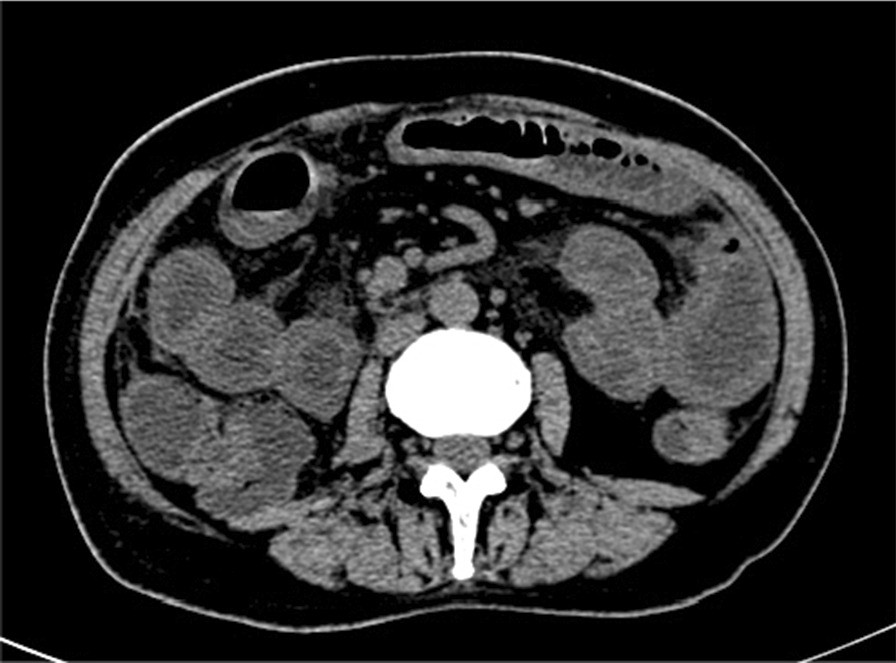

Fig. 3From: Ureteral urothelial carcinoma with squamous cell carcinoma and sarcomatoid carcinoma differentiation: a case reportA cystic shadow can be seen on the right side of the pelvis and the rectum and uterus, with blurred edges and unclear boundaries from the adjacent bowelBack to article page